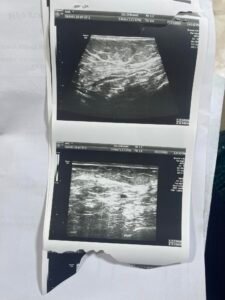

تم اخذ المريضة الى الطبيب المختص واخبرنا ان هناك ورم بسيط في الثدي الاخر وان شاء الله يمكن ان يختفي بالعلاج لكن يجب ان تستمر على العلاج دون انقطاع نهائيا لضمان عدم رجوع المرض او انتشاره في اماكن اخرى. وبحمد الله وفضله تم تأمين وتسليم المريضة الدواء الذي تحتاجه لمدة شهر.